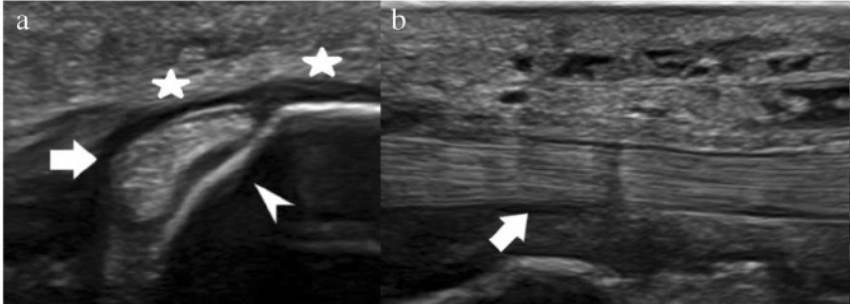

En este otro corte ecográfico de un varón de 39 años, puedes observar otro tendón tibial posterior (TTP) sano:

En el eje corto (imagen A), a nivel del maléolo medial, el tendón (flecha) aparece como un bloque sólido y bien definido sobre el surco óseo (punta de flecha).

Presenta una ecogenicidad uniforme, sin zonas oscuras sospechosas, y está abrazado por un retináculo flexor (estrellas) que se ve como una banda fina y sana.

En el eje largo (imagen B), el tendón (flecha) muestra una estructura fibrillar homogénea y brillante (hiperecoica). Las fibras están perfectamente alineadas. Esa continuidad y brillo son el indicativo de que el tendón está sano.